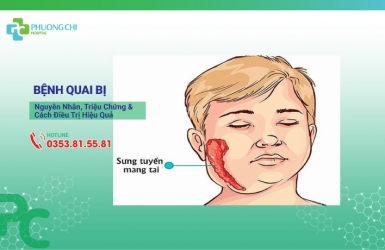

Bệnh Quai Bị: Nguyên Nhân, Triệu Chứng Và Cách Điều Trị Hiệu Quả

Quai bị là một bệnh truyền nhiễm cấp tính khá phổ biến ở trẻ em. Hiện nay, vẫn chưa có thuốc đặc hiệu để điều trị quai bị. Nếu không được chẩn đoán và điều trị đúng cách, bệnh có thể gây ra nhiều biến chứng nguy hiểm.